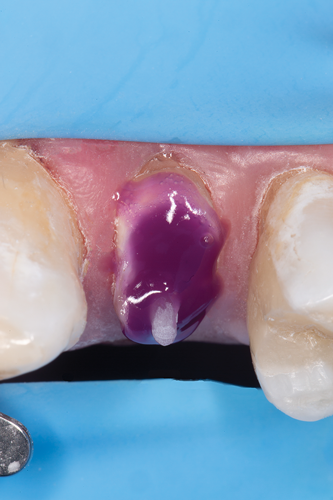

After polymerization and removal of the stopper, the fiber post was cut with a diamond bur to the predetermined length (Figure 17). It should be noted that the clinician should never use a serrated instrument or shears to cut the post to avoid damaging the integrity of the post. The remaining sound tooth structure (ferrule) was etched for 15 seconds with a 37.5% phosphoric acid semigel, rinsed for 5 seconds, and air-dried (Figure 18). With the use of a sable brush, silane was then applied to the coronal portion of the fiber post and existing composite material and air-dried. A universal adhesive was applied to the tooth structure, existing composite material, and fiber post and allowed to dwell for 10 seconds, then air-dried and light-cured (Figure 19).

Fig 18. The remaining sound tooth structure (ferrule) was etched for 15 seconds with a 37.5% phosphoric acid semigel, rinsed for 5 seconds, and air-dried.

Figure 18